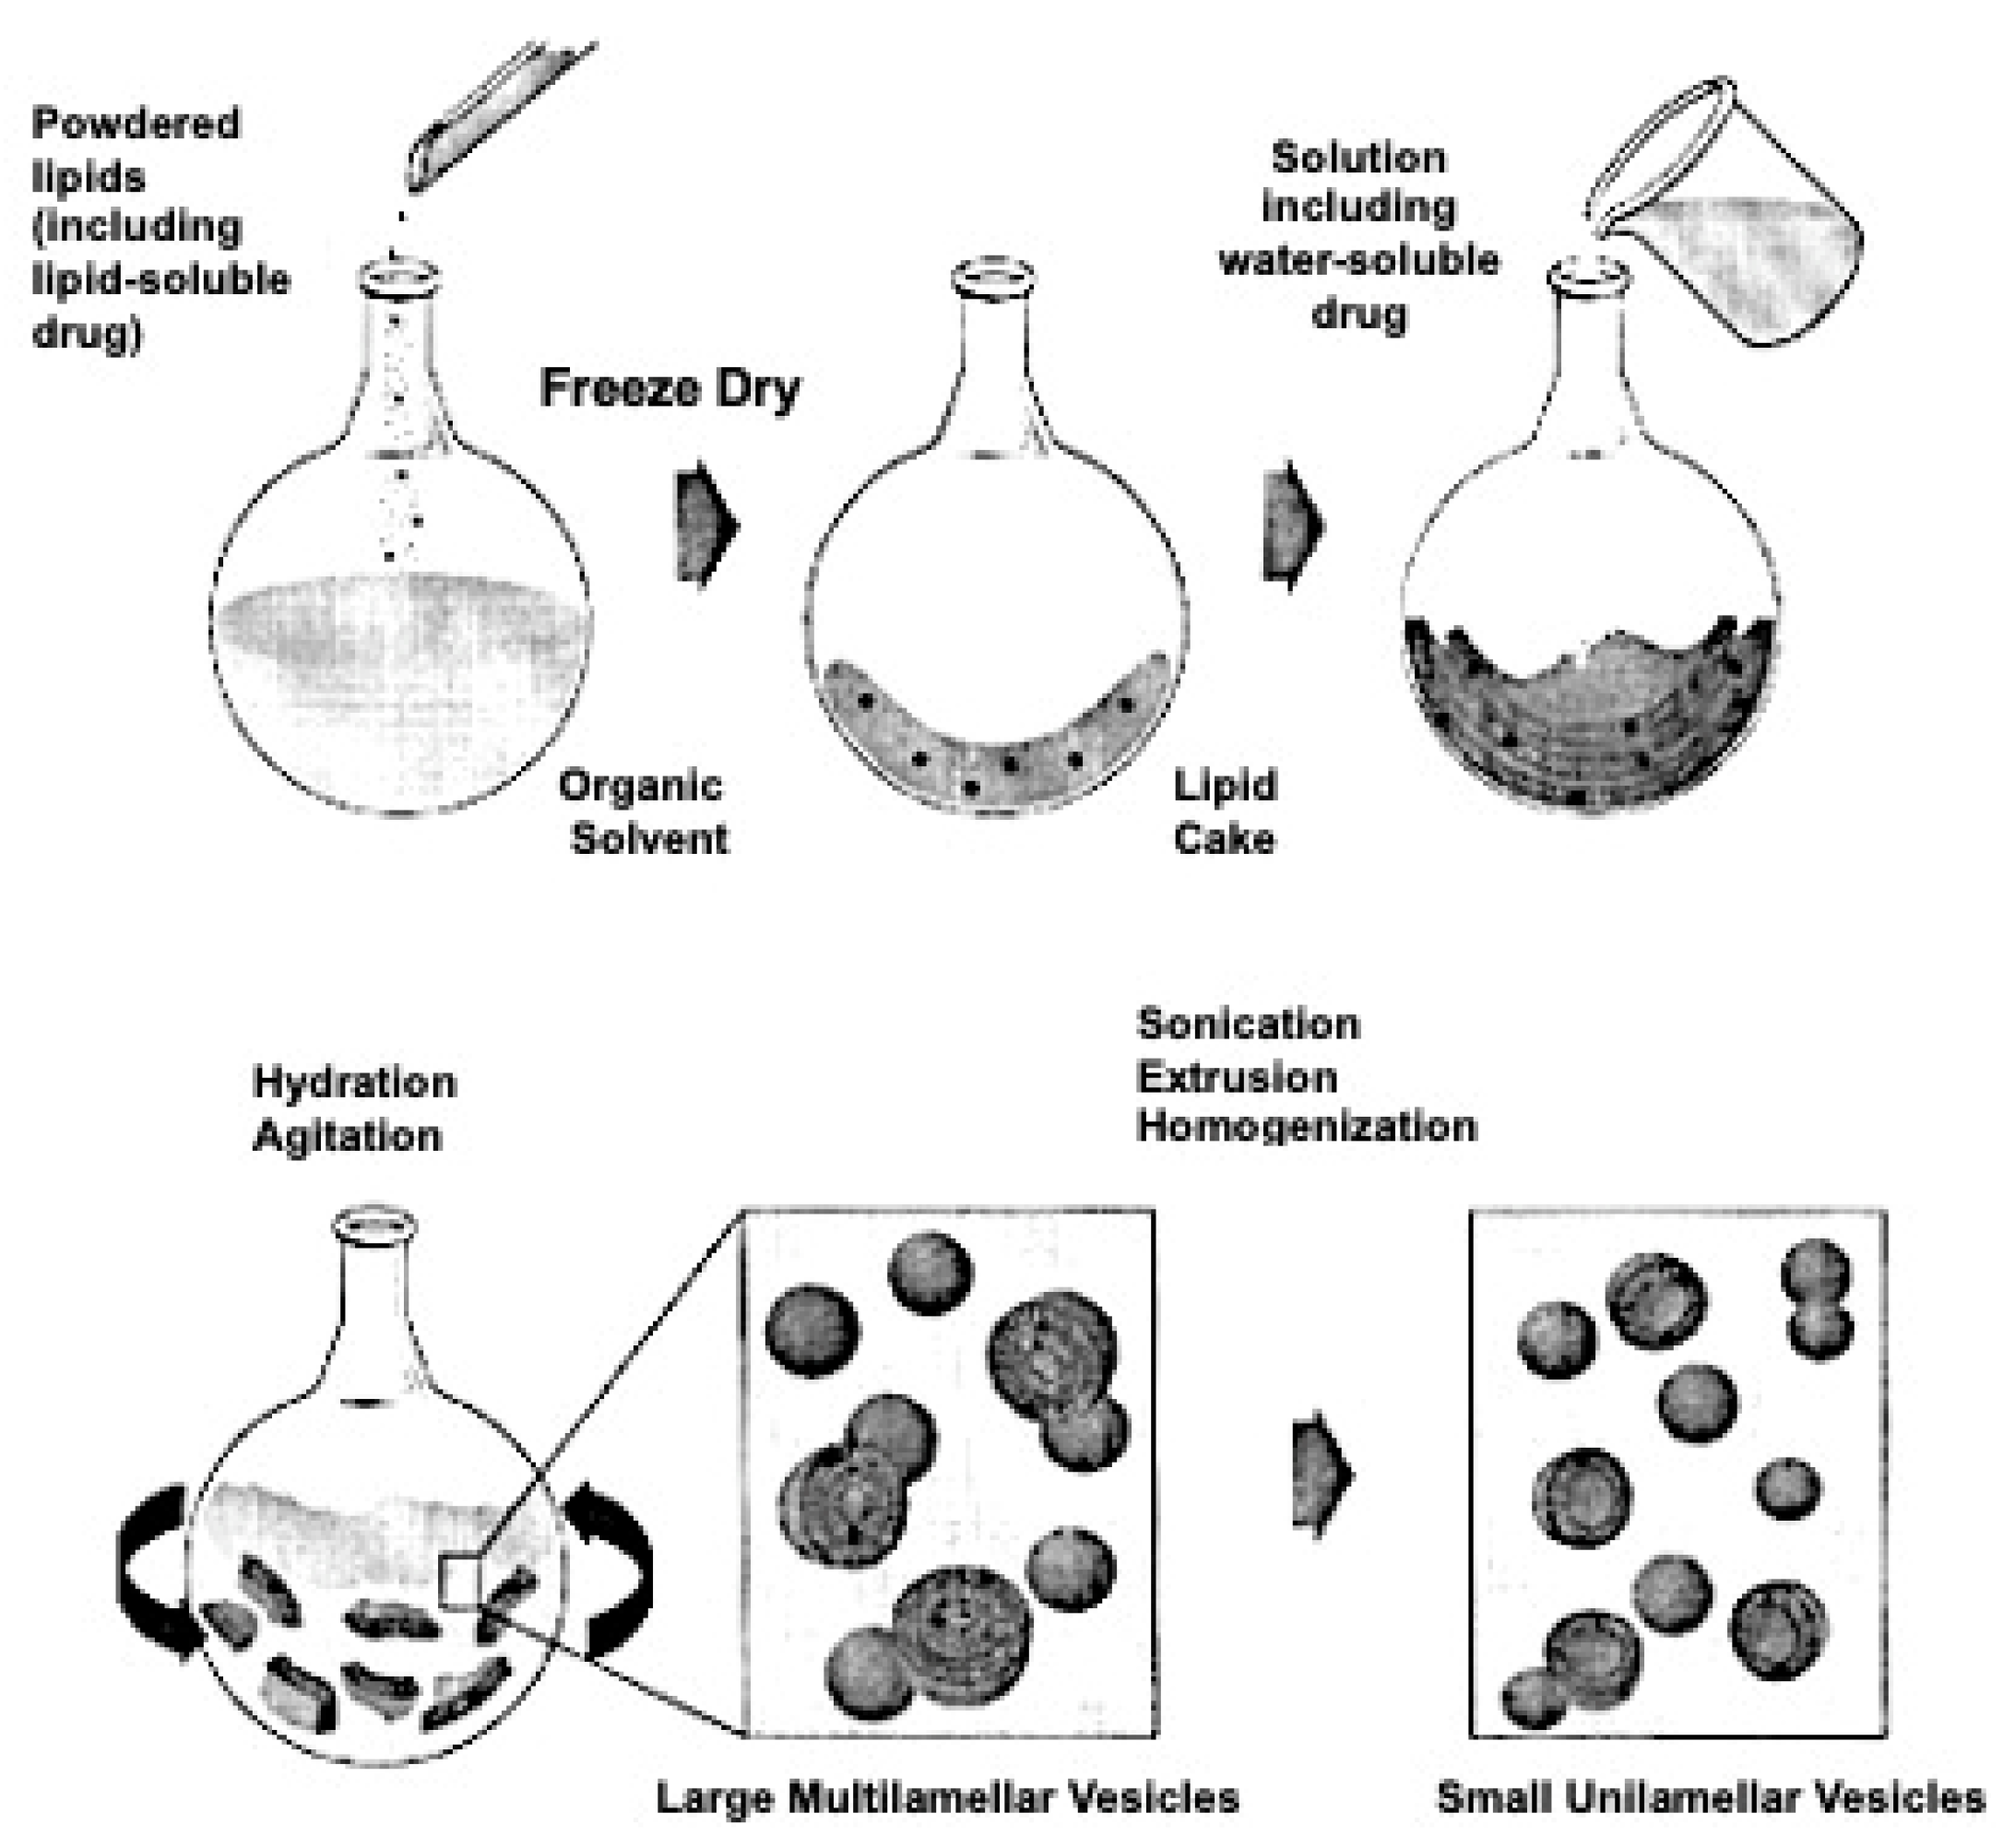

4. Liposomes and Therapeutic Strategies